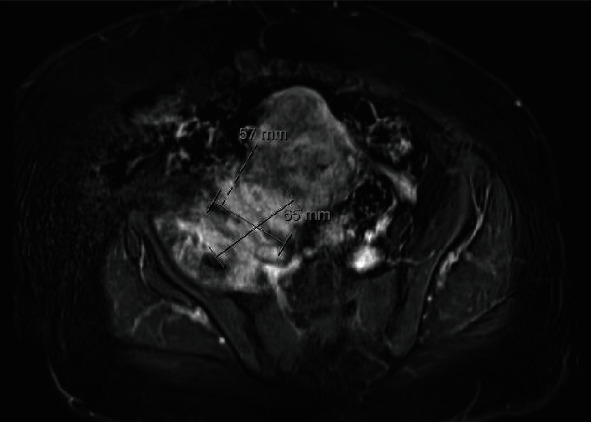

髂腰肌痰肿/脓肿并不常见,患者通常表现为非特异性症状。诊断通常比较迟缓,几乎总是需要先进的成像技术,如计算机断层扫描或磁共振成像。我们报告了一例 51 岁女性的病例,她出现右下肢肿胀并伴有皮疹,造影显示髂腰肌脓肿继发于宫内避孕器感染。这一罕见病例强调了髂腰肌脓肿的非特异性表现,以及在妇女出现髂腰肌痰液和脓肿时考虑宫内避孕器等非正常感染源的必要性。

Iliopsoas phlegmon/abscess is uncommon, and individuals often present with nonspecific symptoms. Diagnosis is often delayed and almost always requires advanced imaging techniques such as computed tomography or magnetic resonance imaging. We report a case of a 51-year-old woman who presented with right lower limb swelling and associated rash with imaging demonstrating iliopsoas abscess secondary to an infected intrauterine contraceptive device. This rare case highlights the nonspecific presentation of iliopsoas abscess and the need to consider unusual sources of infection such as an intrauterine contraceptive device in women presenting with iliopsoas phlegmon and abscess.